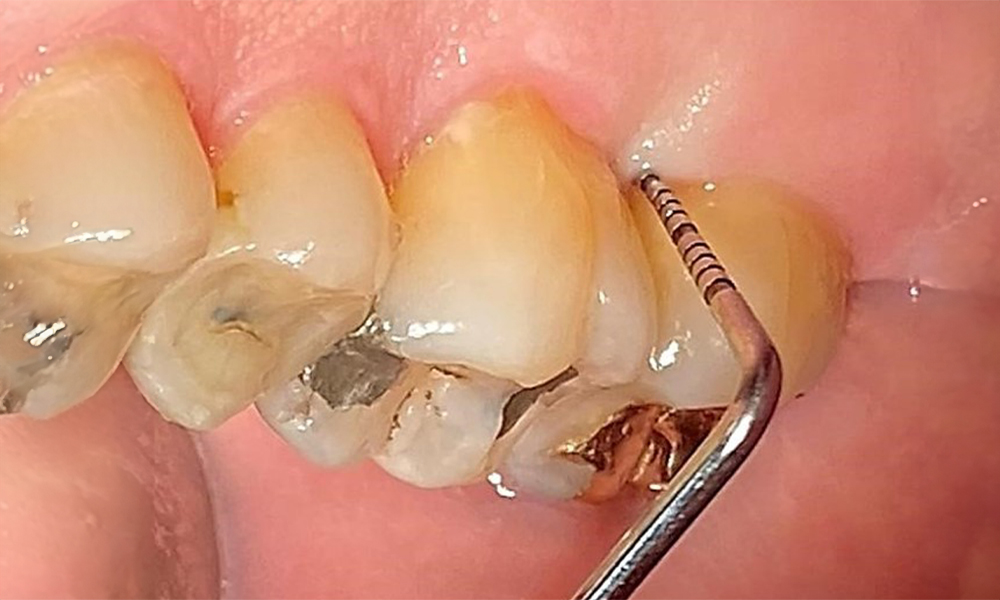

Occlusal view of the maxilla. Insufficient amalgam filling of 14 with a marginal gap.

Fig. 5 Occlusal view of the maxilla. Insufficient amalgam filling of 14 with a marginal gap. © Dr R. Krapf

The patient has a full dentition with 28 teeth, which includes amalgam and composite fillings in the molar and premolar regions. There is a visible clinical marginal gap present on tooth 14. Tooth 27 has an adequate gold inlay. There are also generalized attritions and abrasions. (Fig. 2, Fig. 3, Fig. 4, Fig. 5, Fig. 6)

There are no limitations regarding the choice of instrumentation methods. Regular supragingival and subgingival instrumentation is essential to prevent disease progression due to the pre-existing periodontitis and high risk of recurrence. There are no limitations placed on the selection of instruments for mechanical biofilm removal from a general medical perspective, and removal should be performed as needed. Hard and mineralized plaque, such as calculus and concretions, should be removed using manual instruments or sonic/ultrasonic scalers (Fig. 9) (8, 9).

Use an ultrasonic tip to remove hard, mineralized plaque (Proxeo Ultra scaler with the Perio tip, W&H, shown here).

Fig. 9: Use an ultrasonic tip to remove hard, mineralized plaque (Proxeo Ultra scaler with the Perio tip, W&H, shown here). © Dr R. Krapf